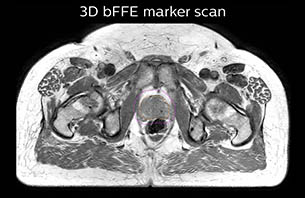

A 77-year-old male with prostate cancer cT3aN0M0, Gleason 8 and PSA 52 μg/L referred to androgen deprivation and radiation therapy with a prescribed dose of 50 Gy to the pelvic lymph node regions and 76 Gy to the prostate.

The 3D T1W FFE mDIXON sequence provides in-phase, water and fat images in one acquisition. Target and organs-at-risk are delineated on the 3D T2W TSE images. Prostate GTV is shown in orange, PTV in purple. The 3D bFFE sequence is used by the planner to mark the position of the fiducial markers (gold anchors) and contours are transferred to the digitally reconstructed radiographs (DRRs).